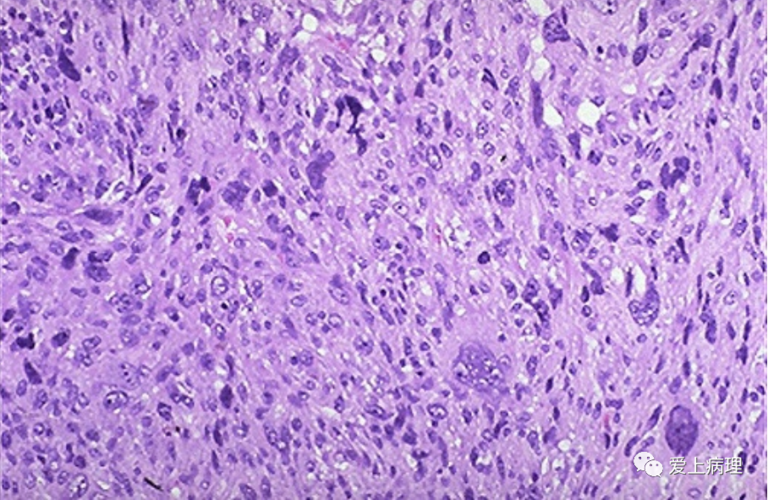

恶性肿瘤-肉瘤

恶性肿瘤图片

恶性横纹肌肉瘤图片

软组织肉瘤